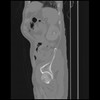

7 CUERPO,CE,Sagittal,3.000,CUERPO,Sagittal,